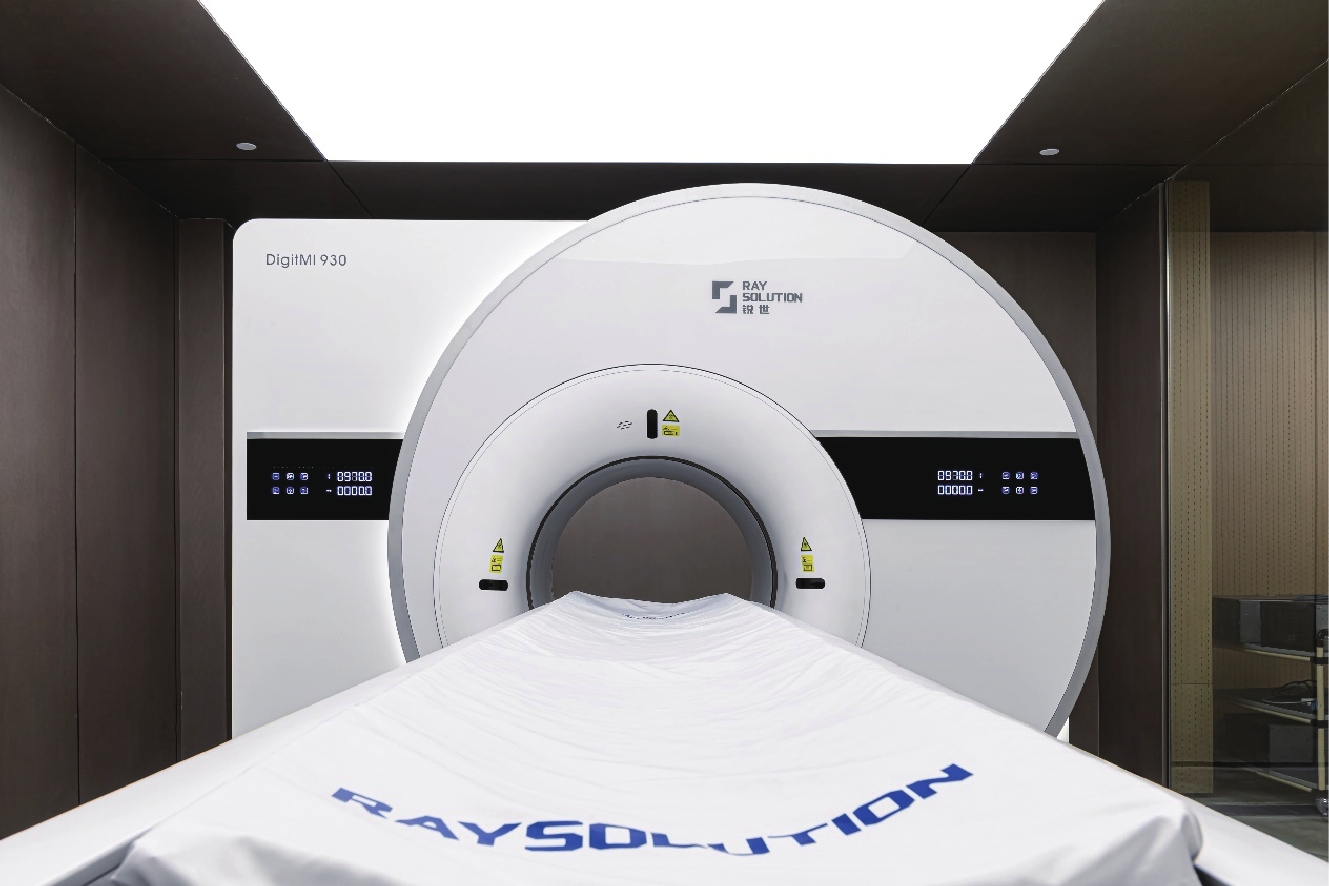

得益于模块化的探测器设计和乐高式的系统架构,临床全数字PET医疗设备的产品研制进入了高速发展期。仅3年时间,第2代临床全数字PET/CT DigitMI 930于2022年取得国家药品监督管理局(National Medical Products Administration,NMPA)三类医疗器械注册证[16]。第2代产品将轴向FOV上扩展到了30.6 cm,且在材料、器件上均进行了更新,在灵敏度、时间分辨率上均进一步提升。临床全数字PET/CT与采用传统技术路线的PET系统相比展现了很强的性能优势,DigitMI 930获得了249 ps的飞行时间分辨率,17.0 kcps/Mbq的系统灵敏度,325.6 kcps的噪声等效计数率。上述优越的物理性能在临床上能支持在0.05 mCi/kg的低剂量下,135 s内完成从颅底到大腿的全身扫描(图2)。

随后的9个月,同样技术路线下的3款临床全数字PET/CT产品DigitMI 920/925/930+相继获得 NMPA三类医疗器械注册证的批准。不同的临床全数字PET/CT均采用通用性的全数字化探测器模块,仅集成不同数量的探测器,通过软件适配和裁剪,形成轴向FOV不同的PET系统,以应对不同的临床需求。

首个面向脑部专用的全数字PET产品DigitMI i30也迅速获得NMPA批准,成为第6款进入市场的全数字PET医疗器械,也是国内仅有的脑部专用PET医疗器械(图3)。由于全数字PET技术架构的灵活性,脑部专用全数字PET原理样机仅用3个月即完成研制[17],并用两个月完成384例科研临床试验[18],开展包括脑胶质瘤、帕金森、阿尔兹海默等8种脑疾病的临床诊断,取得了相对临床全数字PET/CT具有显著空间分辨率优势的图像[19](图4)。i30系统在原理样机上进一步优化,继续采用单PET设计,通过人工智能的训练,无需CT系统,仅使用PET数据即能完成自衰减校正,在性能上展现了极大潜力,是全球首个优于250 ps时间分辨率的脑部PET系统,并具备超过20 kcps/MBq的超高灵敏度。